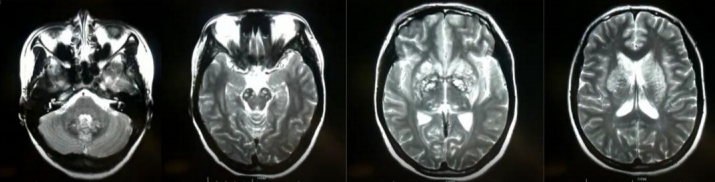

患者女性,26岁,“反复四肢抽搐 11年,言语不利、反应迟钝4天”入院。患者15岁时首次出现癫痫样发作,表现为口吐白沫,头向右侧歪斜,四肢抽搐,伴有意识丧失,持续数秒钟后自行缓解,间隔一段时候后再发,每次发作前多有发热,头痛诱因,诊断为“癫痫”,予德巴金治疗,自行服用半年后停用。患者分别在19岁,21岁,25岁以及今年11月份出现上述癫痫样发作,患者家属诉患者每次癫 痫发作时持续时间均不足1分钟,发作频繁,间歇期逐渐缩短。患者4天前出现言语不利、反应迟钝。

2018.11.3核磁如下:

2018.12.27核磁如下:

2019.1.19核磁如下:

答案:MELAS。其影像典型表现:CT:部分见基底节钙化。MRI:T2WI,FLAIR,DWI序列上相应的高信号;ADC可为高信号,低信号或混杂信号,提示细胞毒性水肿和血管源 性水肿同时存在;磁共振波谱(MRS)提示脑部乳酸的存在。病灶多分布在皮层和皮层下白质,深部皮层不受累;急性到亚急性时期病灶变化可有明显波动,迁移至完全消失;反复发作后脑萎缩。